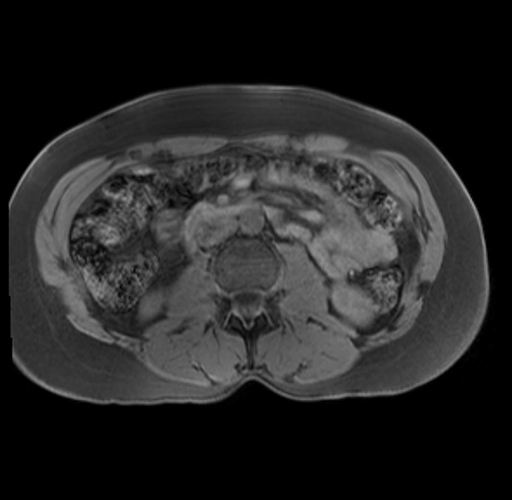

Imaging Analysis

Look through the patient's CT scan to identify any areas of concern for the necessary procedure.

Based on your CT findings, which issue(s) are present and would give reason for "planned slowing down moment(s)" in this case?

Considering a standard distal pancreatectomy procedure, what step(s) of the operation would you do differently in this case?